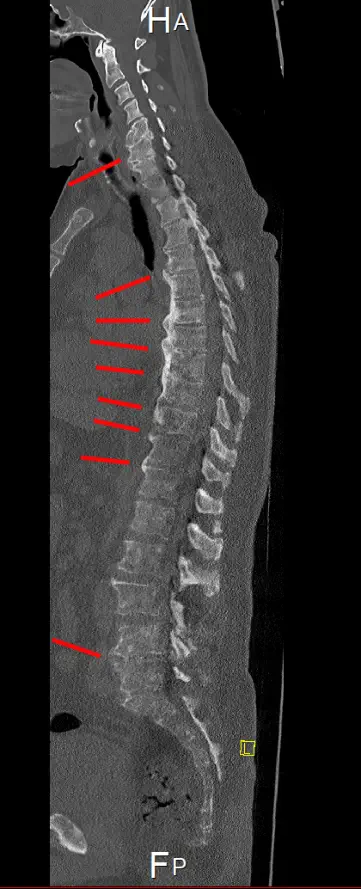

MRT und CT - Bilder - Auswahl

Osteoplastische Knochenmetastasen zeichnen sich dadurch aus, dass Krebszellen den Knochen angreifen und eine übermäßige Bildung von neuem Knochengewebe anregen, was zu einer Verdichtung und Sklerosierung des Knochens führt. Die jedoch die Knochenstabilität nicht verbessert. Die im Gegensatz zu Osteolytische Metastasen bei denen Knochen abgebaut wird. (Zum Beispiel Löcher, dünne Knochen und dünne Knochenränder)

CT vom 24.07.2025